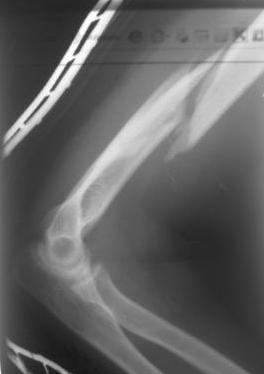

Перелом нестабильный, тактика - если позволяет сосояние больной, оперативное лечение. Как пример см. ниже, можно без скобы - стяжки с ЭПФ.

Представленный способ, функциональный, данная больная в качестве внешней иммобиллизации в течение 3-х недель полльзовалась косыночной повязкой, востановление функции плеча полное. Правда травма изолированная, но операция выполнялась через три недели после травмы, тот час после обращения ко мне - иногородняя.

Уважаемый товарисч.Данный перелом можно вылечить антероградным, ретроградным штифтованием, пластиной, аппаратом внешней фиксации, вытяжением за локтевой отросток на шине ЦИТО. Учитывая наличие тяжелой ЧМТ предпочтение должно отдаваться минимальноинвазивной технике.

Качество паредставленных Вами рентгеновских снимков крайне низкое, что косвенно свидетельствует об общей культуре работы в Вашем отделении.

... Техничски возможно и анте- и ретроградно штифтовать, и открыто и закрыто, а также остеосинтез радиционной пластиной или LCP , и спереди и сзади тоже возможно...

Мы бы, скорее всего, предпочли антеградное штифтование

Спасибо Алексей! Я и планировал провести антеградное штифтование но меня смущал относительно небольшой дистальный отломок. Может для кого-то данные вопросы и кажутся пустяком...но я только недавно начал использовать в своей работе штифты преимущественно Synthes. Еще раз спасибо

Всё правильно, просто я несколько разрозненно пытался сказать на частных примерах, то , что Вы систематизировали. Совершенно верно данный перелом можно и так и эдак, наиболее оптимально антеградное штифтование, хотя я бы предпочёл пластину LCP(просто - ну лучше у меня это получается и всё, а больному не вредит тот же функциональный способ). А низковато для неблокированного штифтования с конструкциями с термомеханической памятью, то, что представленно на втором снимке.